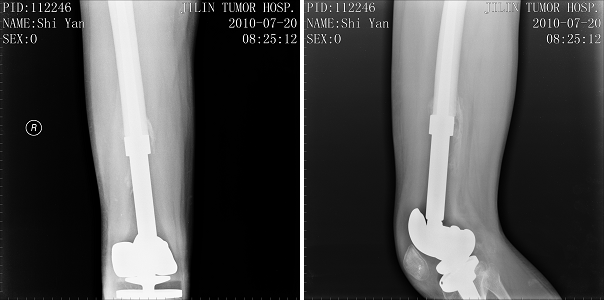

右侧股骨下端骨肿瘤,行右股骨下端骨肉瘤瘤段切除、人工假体置换术。现右膝关节可屈曲至90度,行走自如。